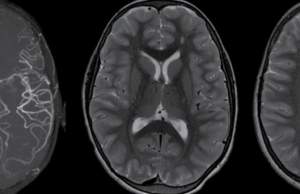

SINDROMUL MOYAMOYA și SINDROMUL DOWN

Moyamoya este o boală cronică ce afectează vasele cerebrale. Vasul afectat se numește artera carotidă internă care irigă creierul, aducându-i acestuia sânge cu oxigen și substanțe nutritive. În boala Moyamoya, artera carotida internă și ramurile sale devin treptat mai înguste, sângele circulă mai greu prin ele, iar în final nu mai circulă deloc.